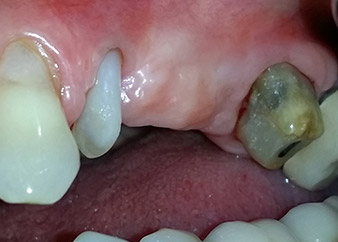

Un mois plus tard, le jour de l'intervention, la douleur et l'inflammation sur la dent 24 étaient minimes mais une mobilité de classe 2 de Miller était toujours observable. Après ouverture des lambeaux et nettoyage des tissus périapicaux et périradiculaires infectés, l'étendue du défaut osseux est devenue parfaitement visible (Figures 2 et 3).

À la racine de la dent, il manquait la totalité de l'os vestibulaire et distal. L'attache était essentiellement limitée à la racine palatine, venant ainsi confirmer le pronostic défavorable initial. La dent 27 présentait également une attache horizontale réduite et une raréfaction apicale minime (cf. Fig. 1), sans symptômes cliniques.

Nous avons toutefois maintenu notre projet initial de conservation des deux dents comme piliers temporaires d'un bridge pendant la période de six mois nécessaire à l'ostéointégration des implants. À la prochaine incision, la situation devrait être réétudiée. Premièrement, afin de gérer le problème endoparodontal, la surface de racine restante a été soigneusement débridée à l'aide d'un équipement piézoélectrique (Piezomed, W&H, utilisé avec l'insert en forme de spatule S1, initialement conçu pour limer la paroi sinusienne latérale) (Fig. 4).